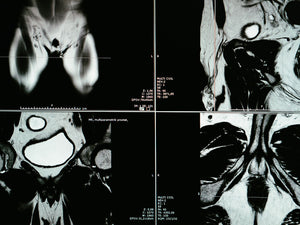

WANN IST EIN MRT SINNVOLL

Mit einem MRT (Kernspin-Untersuchung) lassen sich auffällige Gewebeveränderungen in der Prostata erkennen. Die Untersuchung ist schmerzlos, nicht invasiv und ohne Strahlenbelastung. Sie dauert ca. 20-30 Minuten. Die meisten nationalen und internationalen Leitlinien empfehlen inzwischen ein sogenanntes multiparametrisches MRT (mpMRT*) vor einer ersten Biopsie. Hiermit können die Lage und die Größe eines Tumors sehr gut dargestellt werden. Die Untersuchung hat eine sehr hohe Empfindlichkeit, d.h. kranke Personen werden sehr selten übersehen. Wird im MRT eine Auffälligkeit festgestellt, kann anschließend durch eine zusätzliche gezielte Biopsie festgestellt werden, ob es sich dabei um Krebs handelt. Das MRT kann in manchen Fällen eine Biopsie überflüssig machen und führt in den Fällen, wo eine Biopsie nicht verzichtbar ist zu einer besseren Detektionsrate (Treffsicherheit) eines Prostatakarzinoms.

*Leider werden die Kosten für das mpMRT für die Früherkennung des Prostatakarzinoms derzeit noch nicht von den gesetzlichen Krankenkassen übernommen. Mehr Infos.